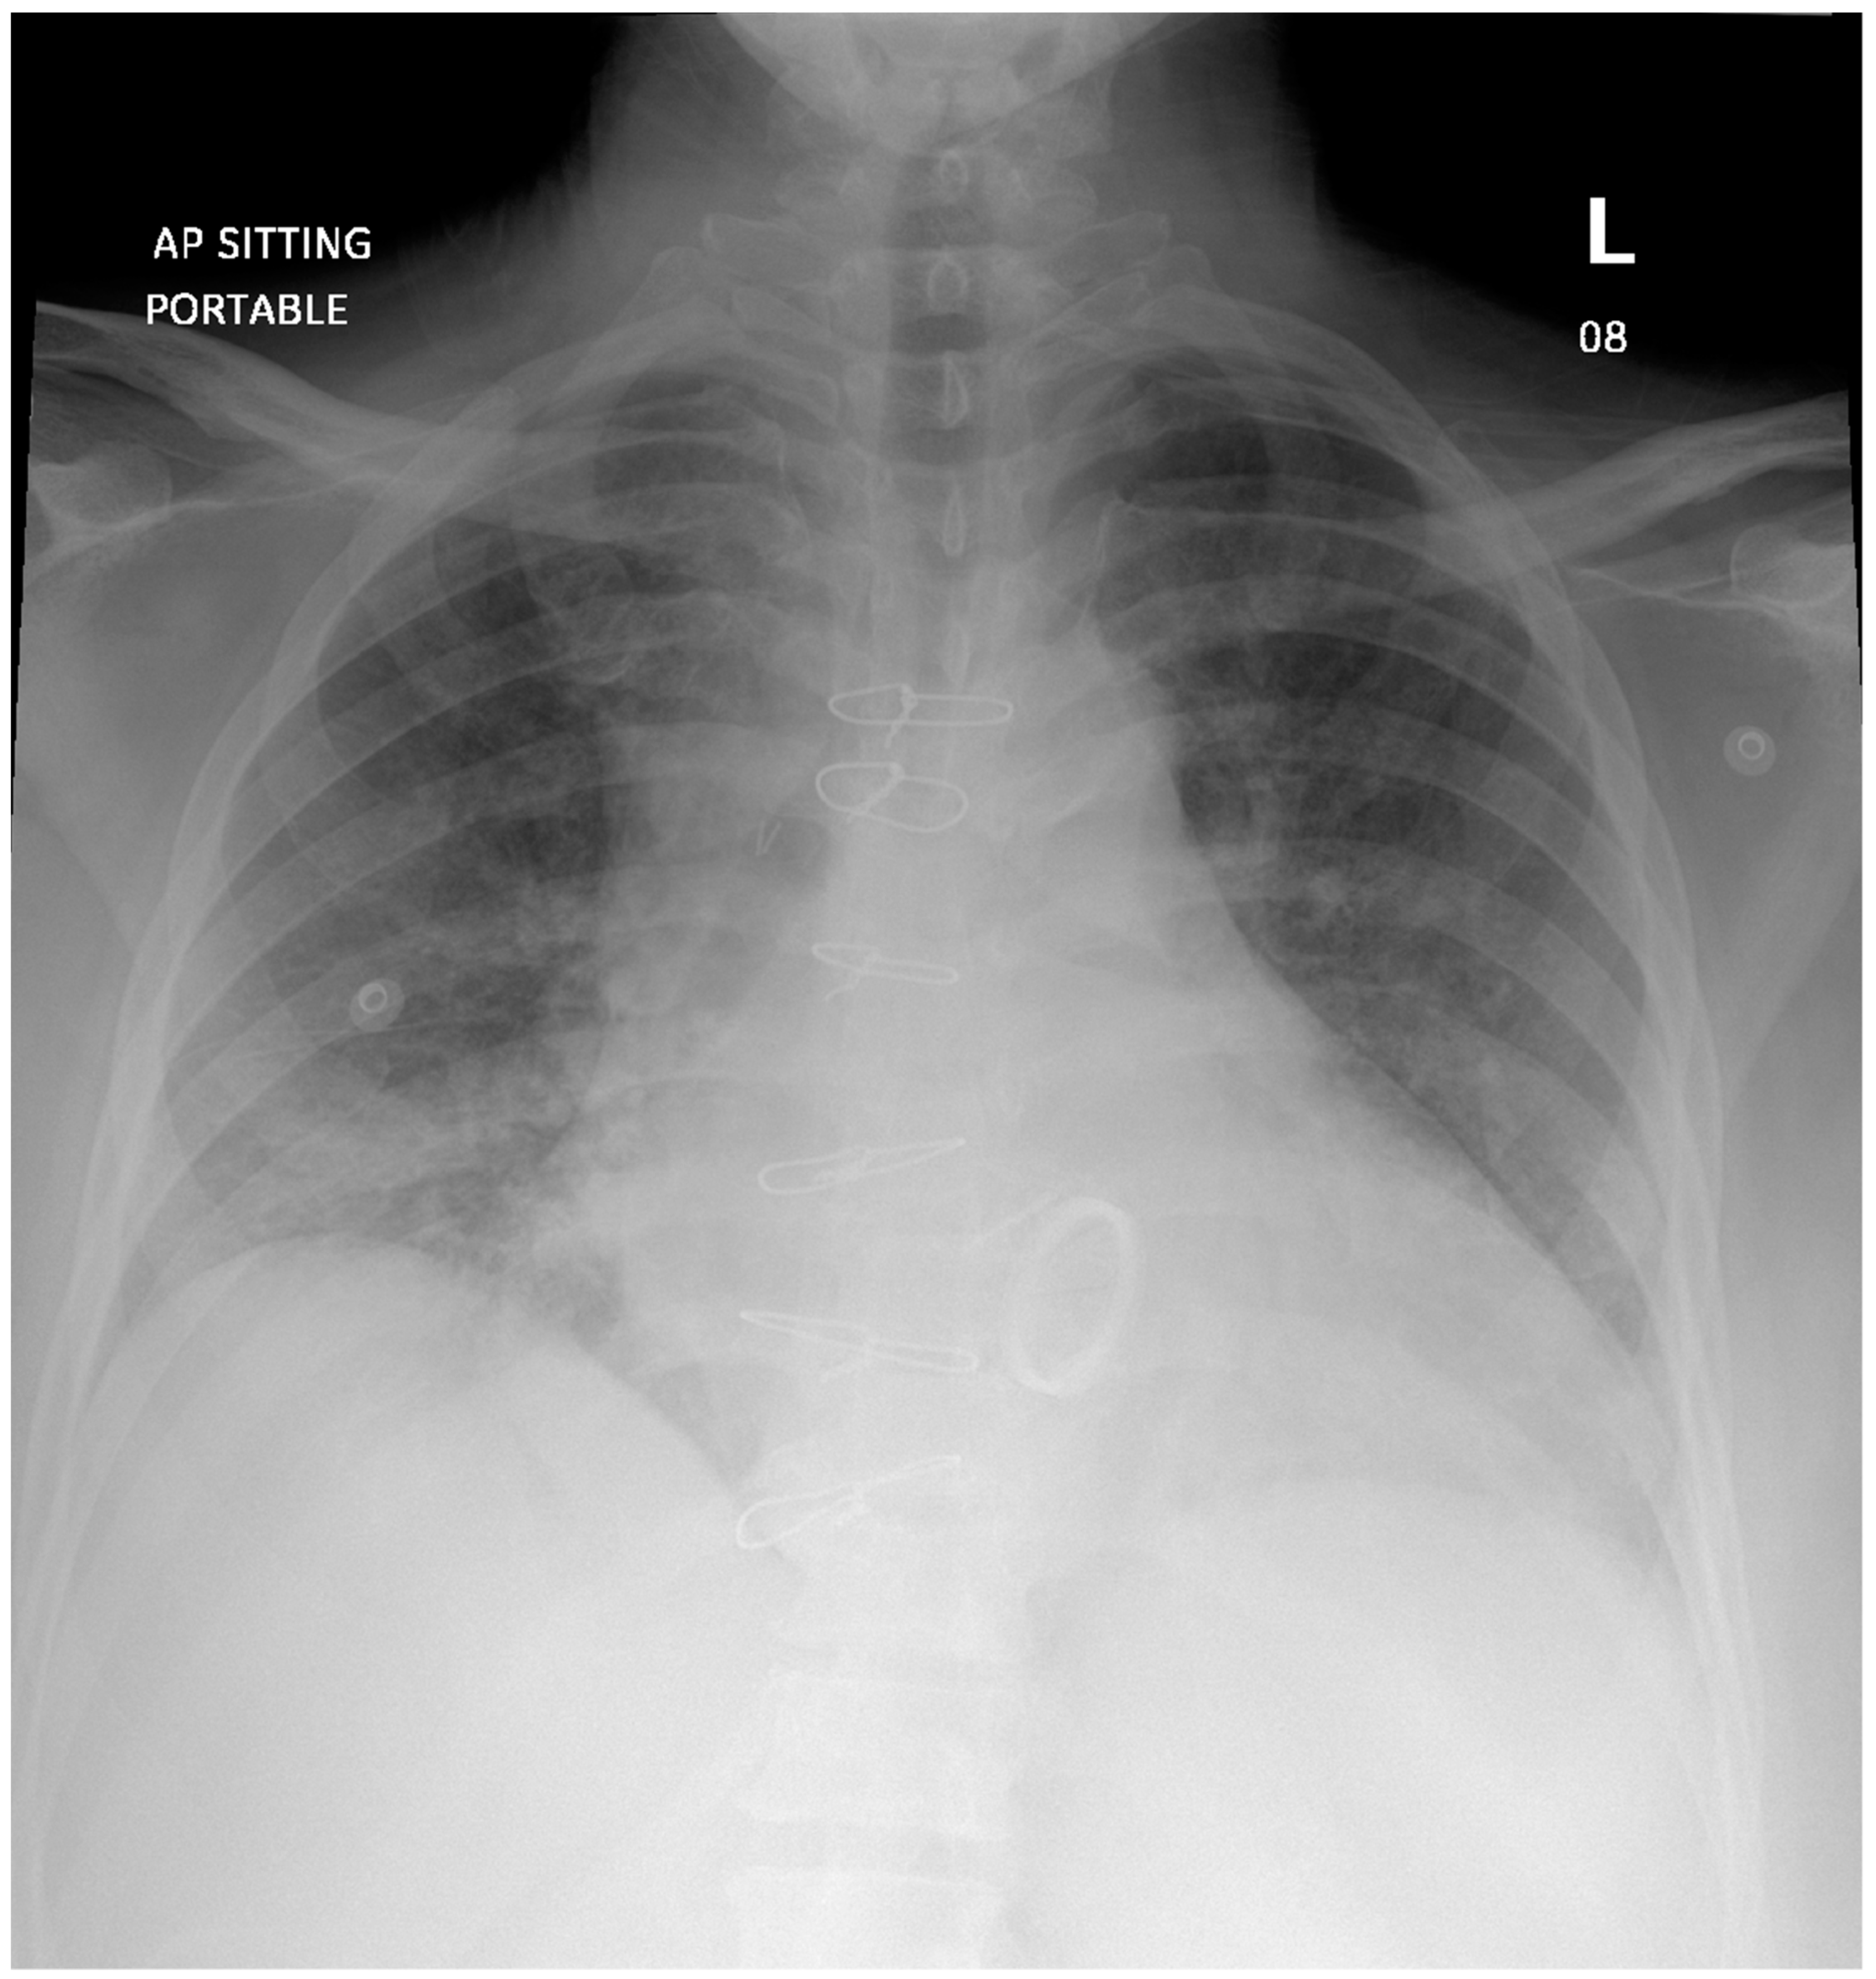

Refractory Salmonella Prosthetic Valve Endocarditis Complicated by Splenic Infarction and Aortic Pseudoaneurysm in a Patient with Double Prosthetic Valves: A Case Report

2. Case Presentation